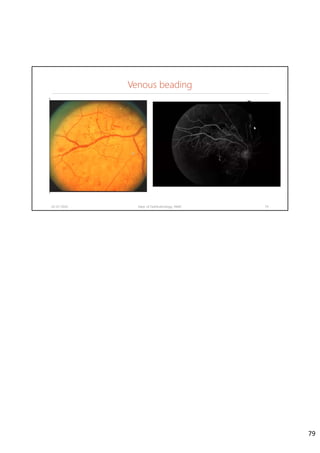

Venous beading

02-07-2020 Dept. of Ophthalmology, JNMC 78

• Major vessels have beaded appearance

• It may be seen in moderate NPDR, but

severity will be less or present only in

one quadrant

• They are very important signs of

worsening Diabetic Retinopathy

78

02-07-2020 Dept. of Ophthalmology, JNMC 79

79